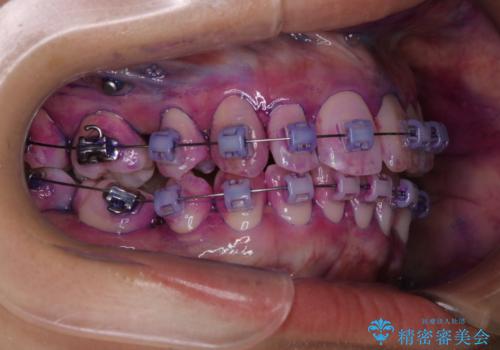

表のワイヤー矯正治療中にPMTCで綺麗に